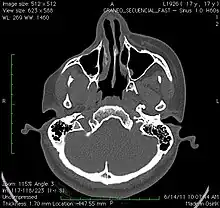

A 3D, soft tissue reconstruction of a CT scan of a 17-year-old girl with Parry Romberg syndrome.

CT scan 3D bone reconstruction of a 17-year-old girl with Parry Romberg syndrome.